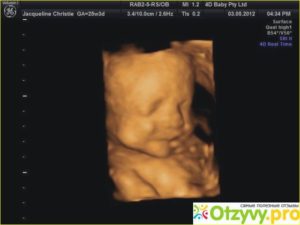

Во время УЗИ можно увидеть, как ребенок сосет пальчик, поворачивает голову, толкается ручками, ножками и даже улыбается.

На 34 неделе беременности плод выглядит так